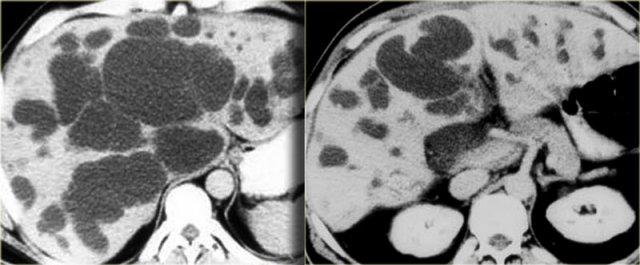

Các dấu hiệu CT giai đoạn muộn được thấy trong các hình ảnh bên trái.

Hãy quan sát các hình ảnh rồi tiếp tục đọc.

Các dấu hiệu bao gồm:

- Thay đổi hình thái xơ gan (mất thể tích thùy phải và thùy đuôi to ra (mũi tên))

- Giãn đường mật rõ hơn